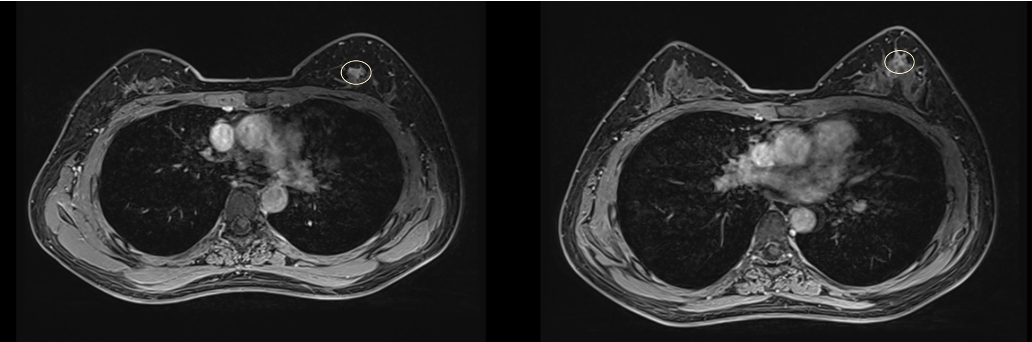

术前MR提示:左侧乳腺内象限及上象限区不规则结节影,最大层面范围约15×11mm,T1W呈等信号,T2W呈高信号,DWI呈弥散受限,增强呈明显强化,动态强化曲线呈速升型,边缘毛躁,符合乳腺癌治疗后改变;双侧腋窝内多个淋巴结。

术前MR